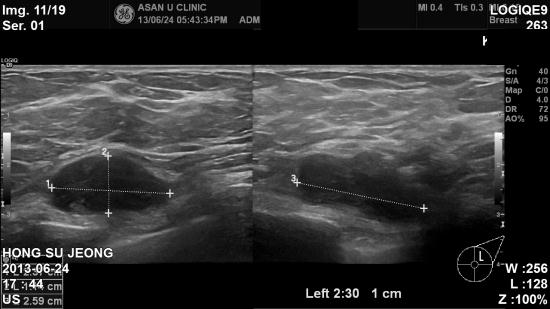

팔에 뭐가 잡혀져 유방을 뒤적이다가 몽우리가 있다고 방문하신

만 76세 여자분입니다.

본원에서 시행한 조직검사상 가장 흔한 유방의 유관암이 아니고

림프종으로 경부종괴에서도

동일한 소견나와 항암치료등 위해 서울아산병원에서 치료예정이십니다.